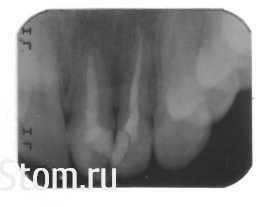

marinchic-tma Опубликовано 25 октября, 2013 Автор Поделиться Опубликовано 25 октября, 2013 Выкладываю фото, и снимок. Снимок был сделан ДО брекетов (01.2012 г.) нового снимка пока нет. После брекетов носила на нижнюю челюсть и до сих пор ношу (на ночь) каппу съемную, на верхнюю тоже носила, но с ней я быстро закончила потому что там и так все ровно. (если нужно фото, то могу выложить).Кстати, еще есть один вопрос, может и глупый но все же, как правильно чистить зубы, по вашему мнению, стоматологи говорят по разному, ТВ лучше совсем не слушать, в интернете разная инфа? и что делать с деснами, наношу метрогил, и полоскаю бальзамом 2 раза в день, но они все ровно кровоточат. зубы.pdf Ссылка на комментарий